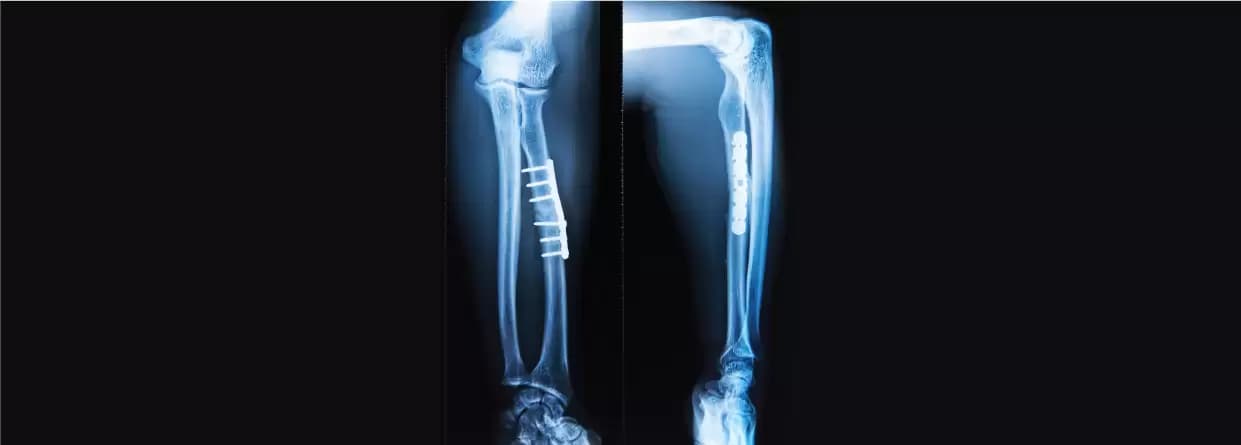

It is one of the treatment methods that the doctor will include. It is recommended when the bones haven’t moved out of their places and the fracture is minor. To treat the problem, there might be a requirement for a cast or splint only. Splinting lasts for more than three to five weeks whereas cast is longer i.e.eight weeks. For both, the doctor will order x-rays to ensure that transverse process fracture recovery is going fine.

The primary cause of transverse fractures is traumas such as accidents and falls, so in severe cases, there might be a need for surgery for bone repair. Some individuals might only require a cast or splint for bone healing.